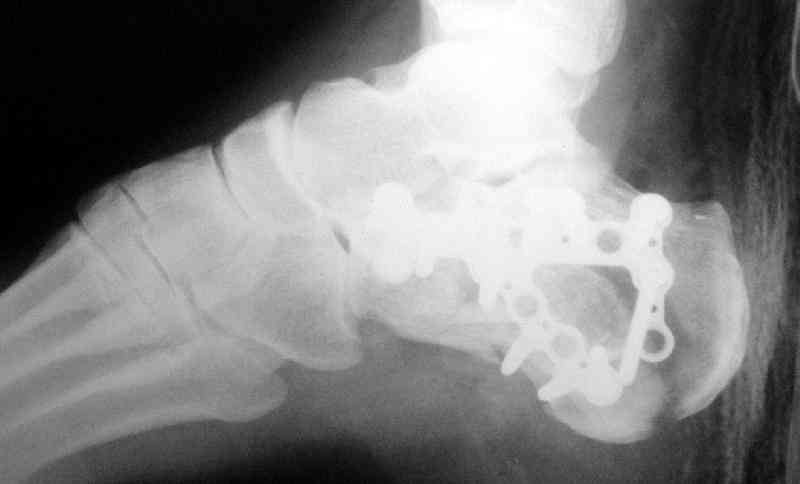

Открытый и закрытый способы лечения.